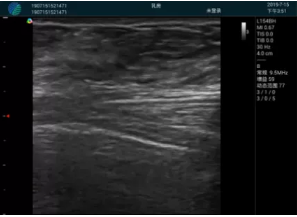

抽吸針進(jìn)入腫塊內(nèi)部進(jìn)行旋切

抽吸過程中可見腫塊明顯縮小,并根據(jù)腫塊位置改變針道位置